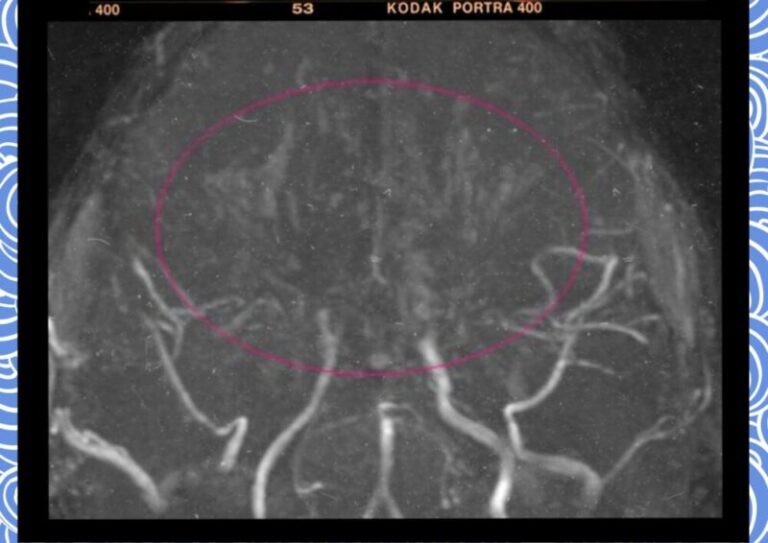

뇌혈관 질환 모야모야병의 숨겨진 위험과 최신 치료법 뇌혈관 질환은 우리 삶의 질을 위협하는 심각한 질병입니다. 특히 그중에서도...

뇌졸중 증상과 대처법 뇌졸중이란 뇌의 일부분에 혈액을 공급하는 혈관이 막히거나(뇌경색) 터짐(뇌출혈)으로써 그 부분의 뇌가 손상되어 나타나는 신경학적...